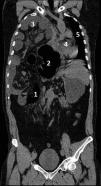

Varón de 49 años, hepatectomizado por quiste hidatídico hace 3 años. Acude a urgencias por dolor intenso en la fosa renal derecha de corta evolución, se realiza analítica: normal; ecografía abdominal: sin hallazgos, y radiografía abdominal (fig. 1): valorada como normal al inicio; tras una revisión describen la ausencia del patrón intestinal, casi en su totalidad, con burbujas aéreas en hipocondrio y fosa ilíaca derechas. Tras estabilización ingresa en planta como cólico nefrítico. A las 24h presenta deterioro clínico, realizándose TC (fig. 2): gran hernia diafragmática (1) con perforación y necrosis del intestino grueso (2) y delgado (3), desplazamiento de todas las vísceras torácicas (4 y 5). En situación de shock séptico refractario se interviene en 3 ocasiones con amplia resección intestinal por isquemia masiva. Mejoría progresiva, actualmente en domicilio, aunque con grave síndrome de intestino corto.